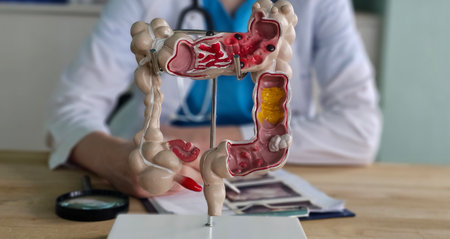

Doctor examines digestive system model and ultrasound image. Stomach intestine ulcers cyst and oncology and examination

A detailed anatomical model depicting human organs displayed atop a modern workspace with office supplies, reflecting themes of medical education and health.

Detailed anatomical model of the human digestive system displayed during a medical consultation in a clinic

A medical professional in a laboratory setting examines a detailed 3D model of the human intestine, highlighting the importance of education and research in healthcare.

Detailed model of the human digestive system displayed in a medical office setting during daytime